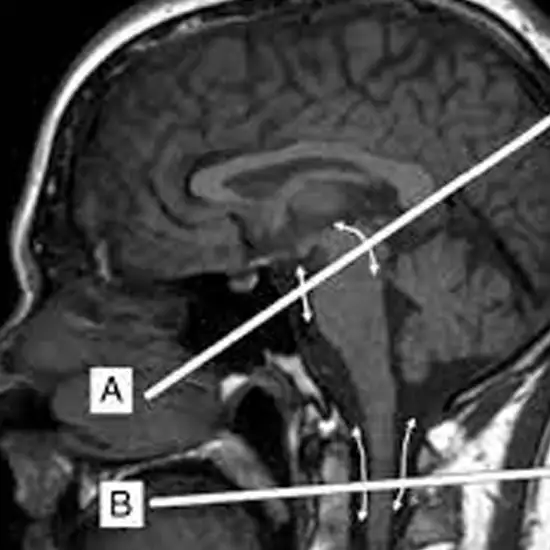

A Magnetic Resonance Imaging (MRI) brain with CSF (cerebrospinal fluid) research generates an image of the CSF's volume, back and forth movement of CSF fluid and surrounding soft tissues.

For the CSF flow evaluation, the two series of phase-contrast imaging techniques are generally applied.

One in axial plane with the through-plane velocity encoding and for the flow quantification, and the other is in sagittal plane, with the in-plane velocity that is encoding for a qualitative assessment.